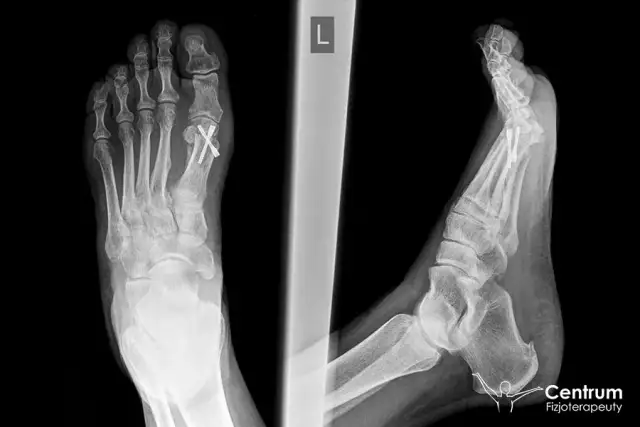

Masz haluksy? Dowiedz się, do jakiego lekarza się udać, jakie badania czekają Cię i jakie są dostępne metody leczenia od zachowawczych po operacyjne.

Poznaj skuteczne ćwiczenia na haluksy! Zmniejsz ból, popraw ruchomość stopy i spowolnij wadę dzięki praktycznemu poradnikowi krok po kroku.

Ile trwa operacja haluksa? Poznaj szczegółowe ramy czasowe zabiegu, pobytu w szpitalu, rekonwalescencji i L4. Przygotuj się na powrót do sprawności!